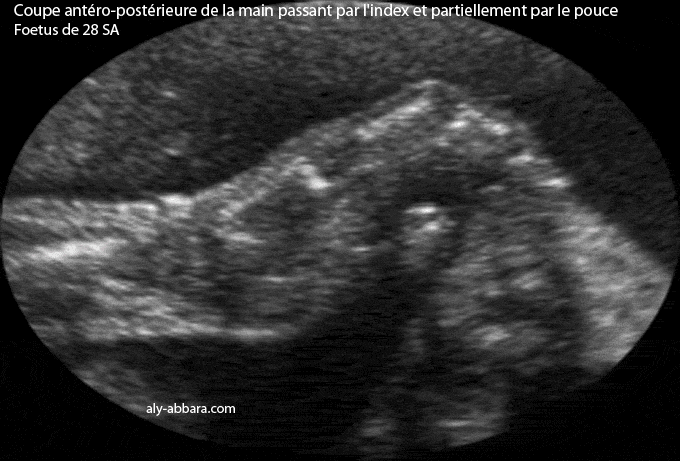

Coupe échographique antéro-postérieure de la main gauche passant dans l'index et partiellement par le pouce. Cette image met en évidence les différentes structures de la main, à savoir, le radius, le poignet (aucune structure ossifiée), le IIe os métacarpien, l'index avec sa phalange proximale (la phalange), sa phalange intermédiaire (la phalangine) et sa phalange distale (la phalangette). Il s'agit d'un fœtus âgé de 35 SA |